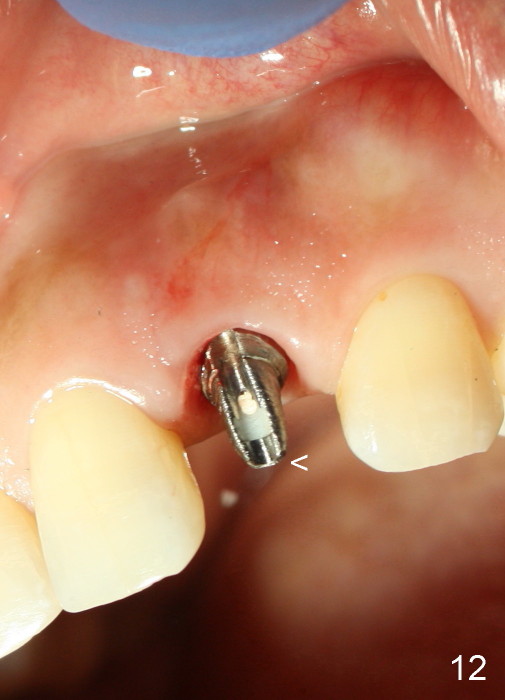

A 49-year-old lady has failed endo on the upper left lateral incisor (Fig.1,2). A gutta percha inserted to the buccal fistula (Fig.1 >) shows a mesial defect (Fig.2<). There is a large buccal apical defect, corresponding to the lesion shown in Fig.2 *, when the affected tooth is extracted. After thorough debridement and Clindamycin soaking, osteotomy is initiated in the palatal wall of the socket. Demineralized freeze dry cancellous bone graft is placed in the buccal defect. A 4x20 mm gingiva-level tapered implant is placed with insertion torque 50 Ncm (Fig.3). A 3x5 mm 20 ° offset abutment is inserted and cemented (Fig.4,5). A retentive groove is prepared on the abutment and the underlying implant; chamfer margin placed on the implant (Fig.4,5). A provisional is fabricated and cemented temporarily (Fig.6,7). Excess cement is removed, followed by removal of gingival retraction cord. There is no contact in centric and non-centric occlusion.

The gingival architecture around the immediate provisional is normal 5 months postop (Fig.10,12). To increase cosmetics for the definitive restoration, the abutment length is reduced (compare arrowheads in Fig.11 to 12).